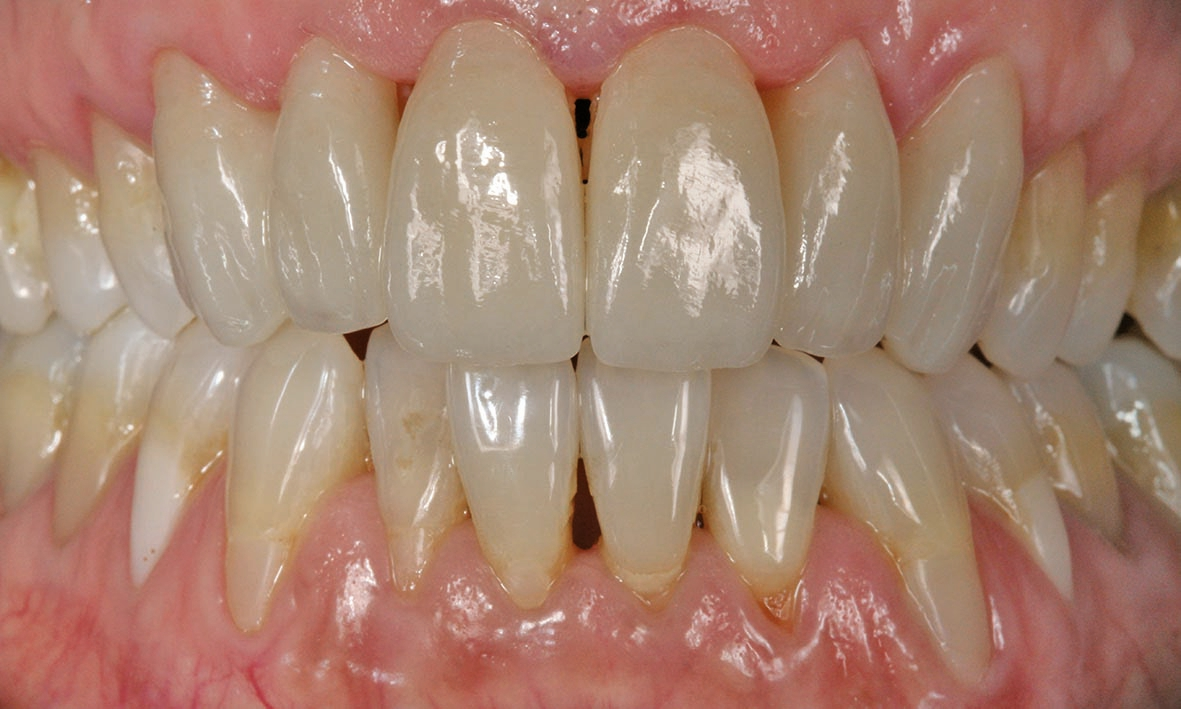

Die fertigen Veneers im Patientenmund

Das Ergebnis hat nicht nur dem Behandler und der Patientin, sondern auch deren privatem Umfeld sehr gut gefallen. Dank der sorgfältigen Analyse, geschickter Materialwahl und eines tollen Behandlungskonzeptes konnten wir die Patientin sehr glücklich machen.